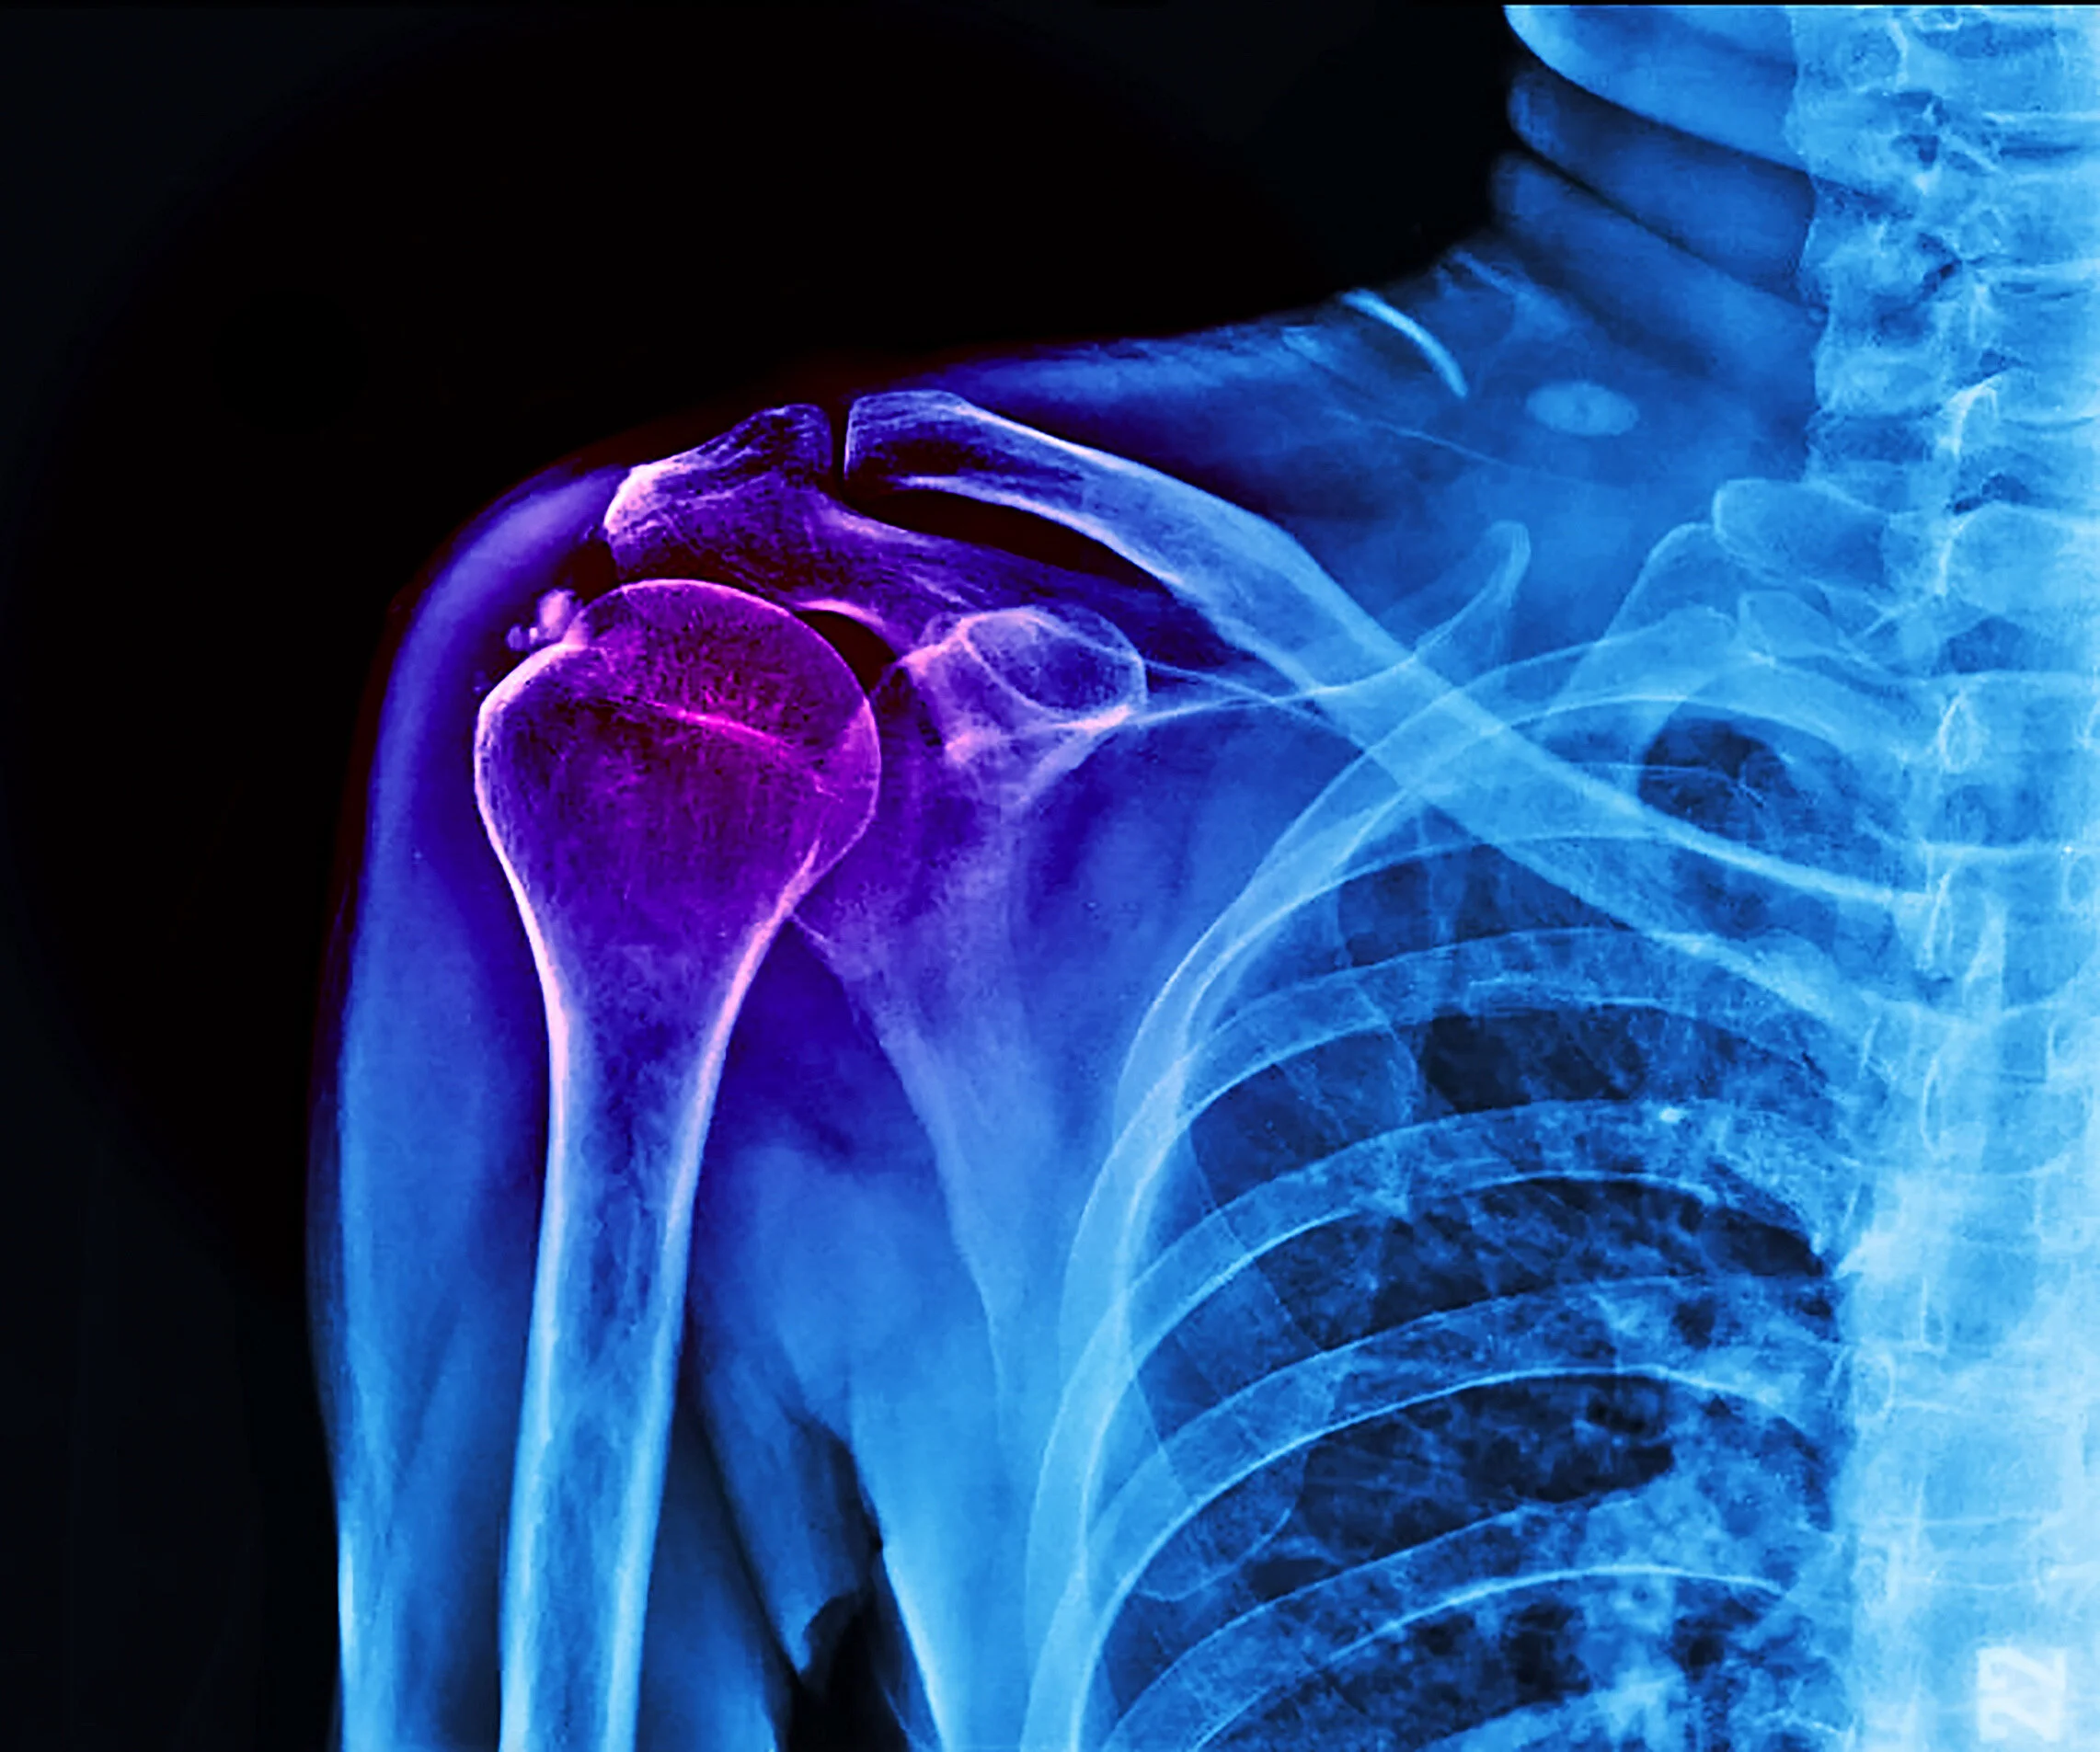

Shoulder Impingement + Bursitis

Shoulder Impingement occurs as the repetitive movement of one of the tendons of the rotator cuff against the coracoacromial arch causing inflammation of the tendons in and bursa in the shoulder. Impingement causes pain with overhead use of the arm and difficulty sleeping on the arm. Initial treatment for Impingement Syndrome is conservative treatment.

Conservative treatment includes activity modification, anti-inflammatories, physical therapy, and often an injection of steroid into the inflamed shoulder bursa.